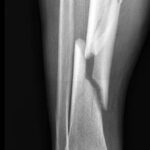

بخشی از نمونه کارها

نمونه کارهای قبل و بعد